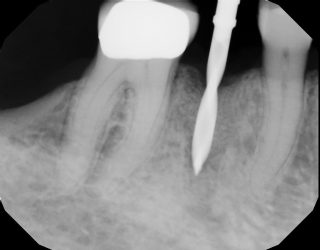

Hey guy, I’m still pretty new to implants. I’ve placed about 30. Looking for suggestions to improve. This is my most recent one. I chose 9 mm implant due to the proximity to the nerve. My main goal was to engage natural bone beyond the apex of the socket without getting too close to the nerve. I used the Densah burs, mostly in OD mode. and…